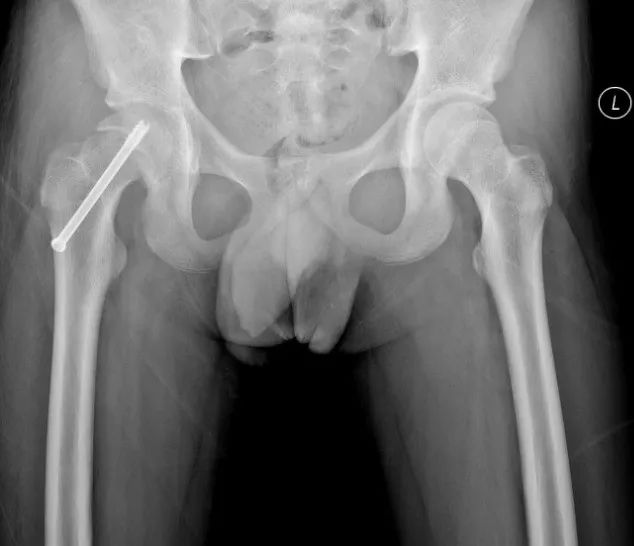

病例2 男,14岁,右侧重度SCFE,行闭合复位,经皮空心钉固定术

病例2 术后17个月复查,X线示位置良好,无股骨头缺血坏死发生